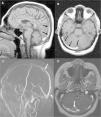

Patient 2A 2.5-year-old boy with no significant past medical history presented to our clinic with puffiness of the eyelids, edema of legs and decreased urine output. He had gained 2kg of weight in a week time. Physical examination revealed facial and pitting edema on extremities in addition to abdominal distension. Laboratory investigations showed Hb 14.9g/dl, htc 45.9%, platelet count 406,000/μL, total protein 3.7g/dl, albumin 1.4g/dl, serum cholesterol 382mg/dl and normal renal function tests. Urinary examination revealed heavy proteinuria; 244mg/m2/h. Serum C3 and C4 levels were normal. Nephrotic syndrome was diagnosed and the patient was put on 2mg/kg prednisone treatment. On the 4th day of treatment the patient complained of headache. Cranial CT was normal. On the 5th day he developed right 6th cranial nerve palsy. Magnetic resonance imaging and MRV showed thromboses in the superior sagittal, right transverse and sigmoid sinuses extending into the jugular system (Fig. 2). Intravenous hydration, low molecular weight heparin (LMWH) were started immediately. Screening for inherited thrombophilias was negative. On 10th day patient's headache subsided, focal neurological signs resolved. Remission was achieved on the 14th day of steroid treatment. The patient was discharged on steroid and LMWH. He had complete neurological recovery and has not experienced any complication during follow-up for 6 months.